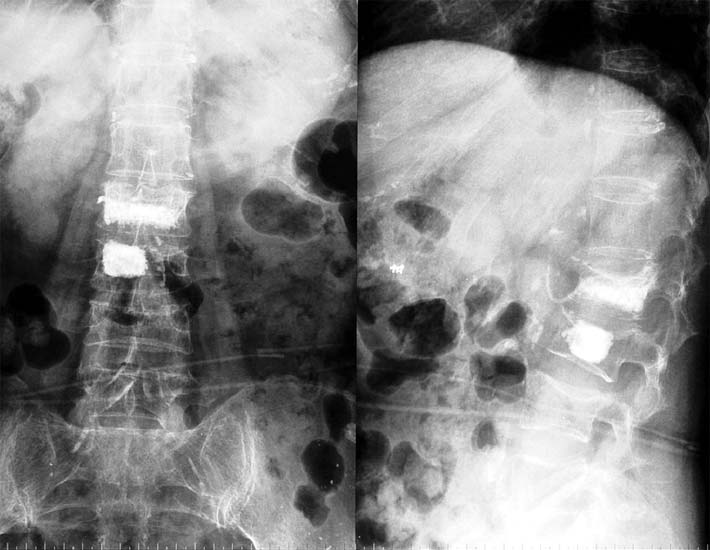

75岁女性,腰椎2、3压缩骨折2个月,疼痛明显

将骨水泥注射到骨折塌陷的两个椎体,迅速止痛,当天下地活动